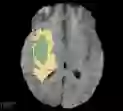

Deep neural network models used for medical image segmentation are large because they are trained with high-resolution three-dimensional (3D) images. Graphics processing units (GPUs) are widely used to accelerate the trainings. However, the memory on a GPU is not large enough to train the models. A popular approach to tackling this problem is patch-based method, which divides a large image into small patches and trains the models with these small patches. However, this method would degrade the segmentation quality if a target object spans multiple patches. In this paper, we propose a novel approach for 3D medical image segmentation that utilizes the data-swapping, which swaps out intermediate data from GPU memory to CPU memory to enlarge the effective GPU memory size, for training high-resolution 3D medical images without patching. We carefully tuned parameters in the data-swapping method to obtain the best training performance for 3D U-Net, a widely used deep neural network model for medical image segmentation. We applied our tuning to train 3D U-Net with full-size images of 192 x 192 x 192 voxels in brain tumor dataset. As a result, communication overhead, which is the most important issue, was reduced by 17.1%. Compared with the patch-based method for patches of 128 x 128 x 128 voxels, our training for full-size images achieved improvement on the mean Dice score by 4.48% and 5.32 % for detecting whole tumor sub-region and tumor core sub-region, respectively. The total training time was reduced from 164 hours to 47 hours, resulting in 3.53 times of acceleration.